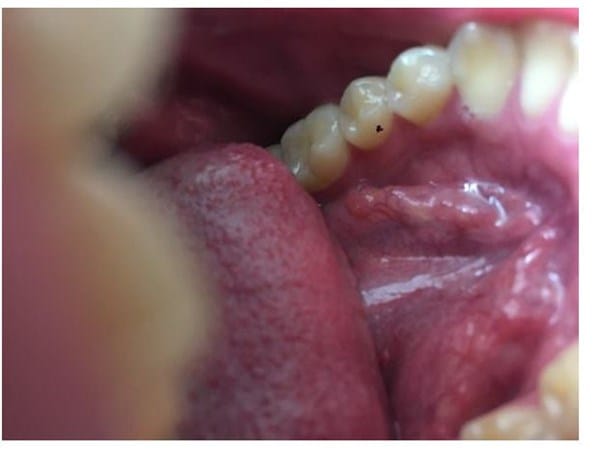

Asi estaba el año pasado justo apenas se ve donde esta el punto negro como un centimetro mas abajo

Luego ayer estaba asi no se si se aprecia un poco transparente

hoy parece que esta como mas clara en el centro pero como roja a los bordes ayudenme,,, por favor segun lei puede ser una ranula o mucocele y si eso hay que explotarlo o se quita solo ayudenme tengo miedo estoy traumado con el cancer desde que mi mama ha pasado por uno y luego que un amigo de mi papa se muriera de un cancer en la boca o algo asi he estado traumado con esto